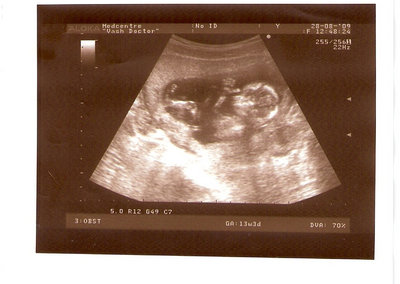

СЫН

| Вложения: |

2.jpg [ 110.14 КБ | Просмотров: 2447 ]

Nikisa писал(а): Foto prosto chudesnoe. A na kakom sroke uznali, chto sin.............. НА 13 НЕДЕЛЯХ.КАК РАЗ ВОТ В ЭТО узи, ОНО УМЕНЯ ВТОРОЕ БЫЛО. ЭТО КОНЕЧНО МАЛЕНЬКИЙ СРОК ДЛЯ ОПРЕДЕЛЕНИЯ ПОЛА. НО Я ПОПРОСИЛА ВРАЧА(ЭТО КТСТАТИВ РОССИИ БЫЛО) ХОТЯ БЫ ПРЕДПОЛОЖИТЬ. ЕЙ ВСЁ ТАКИ УДАЛОСЬ РАССМОТРЕТЬ.НУ ВООБЩЕМ ЧЕРЕЗ НЕСКОЛЬ ДНЕЙ ПОЙДУ К ВРАЧУ, УЖЕ АМЕРЕКАНСКОМУ И УЗНАЮ ТОЧНО. К ТОМУ ВРЕМЕНИ У МЕНЯ БУДЕТ СРОК 18 НЕДЕЛЬ. ХОТЕЛОСЬ БЫ ПОСМОТРЕТЬ НА ДРУГИЕ ФОТО НА ЭТОМ СРОКЕ ИЛИ БОЛЬШЕ. ТАК ЧТО ВЫКЛАДЫВАЙТЕ, ЕСЛИ НЕ ЖАЛКО!